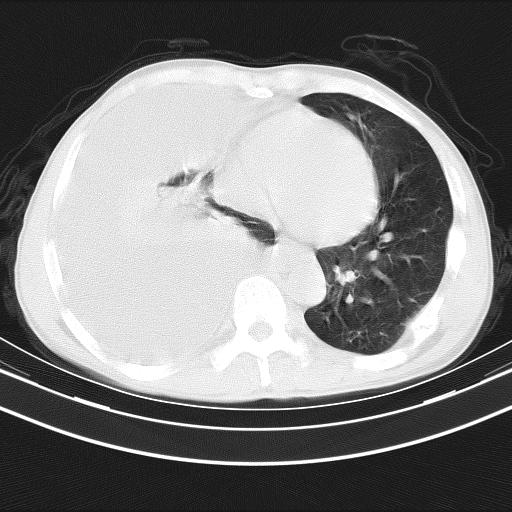

男性,44岁,结核病史多年。现胸闷气短,咳嗽,偶咳血。

右侧胸腔积液

右肺下叶不张

双肺多发结节影最分空洞形成考虑占位不除外结核

双肺陈旧性病变

1、右侧大量胸腔积液伴右肺压缩性膨胀不全,建议抽液治疗后复查 2、两肺继发性tb伴空洞形成。

1)两肺继发性肺结核伴空洞形成,左肺多发性结核球。2)右侧大量胸腔积液伴右肺部分膨胀不全。3)纵隔淋巴结肿大。

1,双肺多发结节 并空洞影改变, 左侧胸腔积液并部分包裹, 结合原病史首先考虑结核. 但也不除外其它.

2,左侧有一根肋骨陈旧性骨折? 建议追查 .